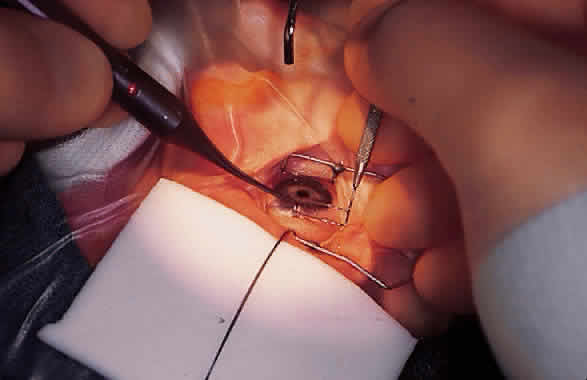

Fig. 8. Trabeculotomy ab externo. A. The surgeon is creating a radial incision in the bed of the partial-thickness scleral flap with a microsurgical blade. B. The dissection is carried downward layer by layer until Schlemm's canal is unroofed. C. Schlemm's canal can be positively identified by cannulation with a 6-0 nylon suture. D. Intraoperative photograph demonstrating cannulation of Schlemm's canal with a 6-0 nylon suture. Note the subconjunctival hemangioma in this eye with Sturge-Weber-associated glaucoma.

A short length of 6-0 black nylon suture material should be used to cannulate Schlemm's canal. The cut end of the suture can easily be smoothed by the application of heat from a disposable battery-operated cautery. The nylon suture must not be forcibly introduced into Schlemm's canal, lest a false passage be created. The suture will pass easily if Schlemm's canal is correctly cannulated, and intraoperative gonioscopy with either a Koeppe lens (Fig. 9) or a Zeiss four-mirror gonioprism (Fig. 10) can be used.